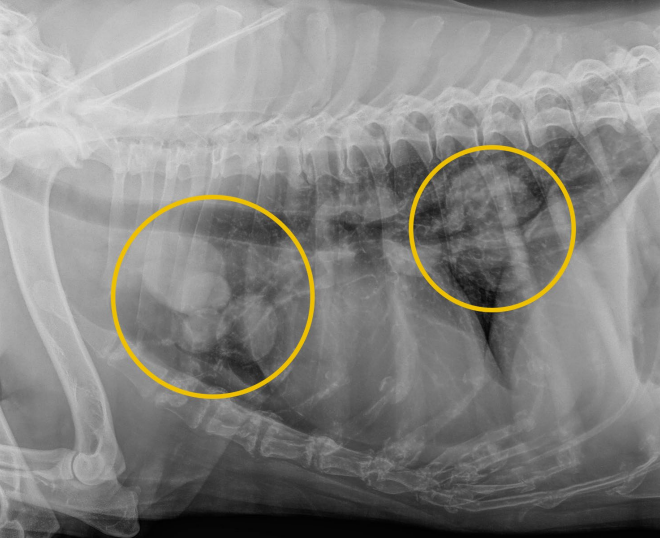

![]() | - 폐전이가 나타남. - bone lysis를 일으키면서 주변으로 전이됨. |